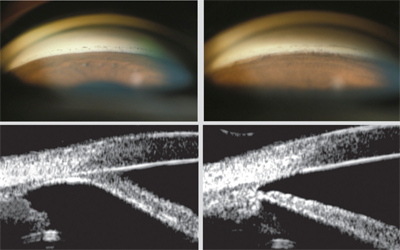

4. 전방각 유착해리술 Goniosynechialysis

급성 폐쇄각 녹내장 발작이 수차례 반복된 경우,

수술이나 외상등에 의해서 발생한

주변부 홍채유착(Peripheral anterior synechia, PAS)이 180도 이상 걸쳐있는 경우에는

수술적으로 전방각을 막고 있는 주변부 홍채를 떼어낼수 있습니다.

이를 전방각 유착해리술, Goniosynechialysis 라고 합니다.

이러한 유착이 최근에 발생하였을수록 수술적 결과가 좋습니다.

너무 오래된 유착의 경우는 수술적으로 유착을 박리하더라도

안압 하강 효과가 적거나, 유착자체가 박리가 잘안되는 경향을 보입니다.

대부분은 백내장 수술을 시행하면서 같이 시행하게되고,

전방각경이 있으면, 전방각경으로 전방을 직접 관찰하면서 시행해야 조직손상으로 인한 출혈을 최소화 할수 있습니다.